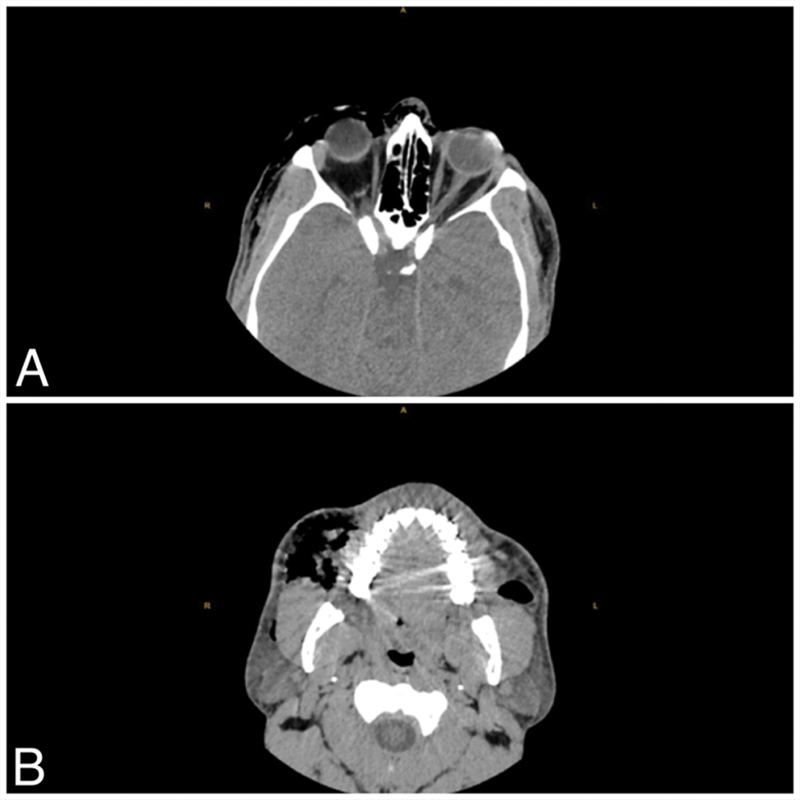

一位41岁男性患者在双侧上、下眼睑成形术4天后出现右眼突然肿胀、发红和疼痛。这些症状之前有强烈的擤鼻症状。经检查,观察到眶周水肿和皮下crepit,同时向上凝视受限。计算机断层扫描显示双侧上颌前和外腔空气积聚。由于没有视神经缺血或眶间室综合征,因此密切监测患者。随访中观察到肺气肿自发消退。眼眶肺气肿,虽然通常与外伤有关,但也可以由剧烈的运动引起,如严重的擤鼻,正如这个独特的眼睑成形术后病例所证明的那样。手术过程中的结构改变可能导致支撑减弱,使患者在压力突然变化后易患肺气肿。临床医生应警惕面部手术后的眶周水肿和皮下crepit,强调及时影像学诊断的重要性。开展宣传活动,建议在术后初期不要采取打喷嚏、咳嗽和擤鼻涕等强烈行为,这对于预防潜在的并发症至关重要。

A 41-year-old man presented with sudden-onset swelling, redness, and pain in the right eye, 4 days after bilateral upper and lower eyelid blepharoplasty. The symptoms were preceded by a forceful nose-blowing episode. Upon examination, periorbital edema and subcutaneous crepitus were observed, along with limitations in upward gaze. Computed tomography revealed bilateral premaxillary and extraconal air accumulation. Since there was no optic nerve ischemia or orbital compartment syndrome, the patient was closely monitored. Spontaneous regression of the emphysema was observed during follow-ups. Orbital emphysema, although commonly associated with trauma, can also arise from compelling movements such as severe nose-blowing, as demonstrated in this unique case postblepharoplasty. The structural changes during surgery may contribute to weakened support, predisposing patients to emphysema following sudden pressure changes. Clinicians should be vigilant for periorbital edema and subcutaneous crepitus after facial surgeries, emphasizing the importance of timely imaging for diagnosis. Awareness campaigns advising against forceful actions like sneezing, coughing, and nose-blowing during the initial postoperative period are crucial to prevent potential complications.